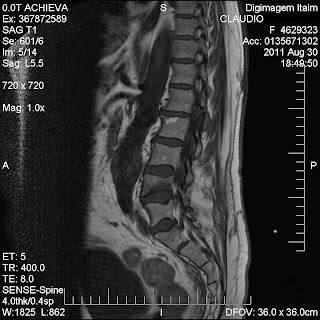

Exame físico, e exames complementares como RX, Ultra-som e Ressonância Magnetica.